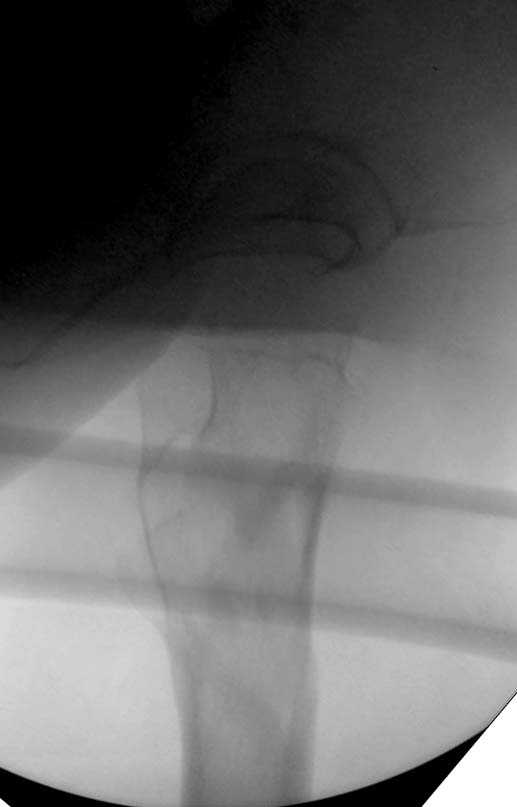

Здесь представлен случай, где в послеоперационном периоде обнаружена техническая ошибка, Gamma 3 установлен с нарушением методики. Больная в 91 лет, прооперирована через день после поступления и выписана через 48 часов.

При первом послеоперационном поликлиническом осмотре больная предъявила жалобы на боли в бедре. В серийных снимках обнаружен продольный перелом верхнего отдела бедра.

Считаем, что техническая ошибка произошла во время установки гвоздя, когда рассверливанию канала не уделили должного внимания. Канал остался узковат, и гвоздь был забит с силой. Полная нагрузка конечности приостановлена на две недели, и боли в конечности изчезли. Больная начала нагрузку и перелом срастается.-- Djoldas Kuldjanov, M.D.Associate ProfessorDepartment of Orthopedic SurgerySt. Louis University